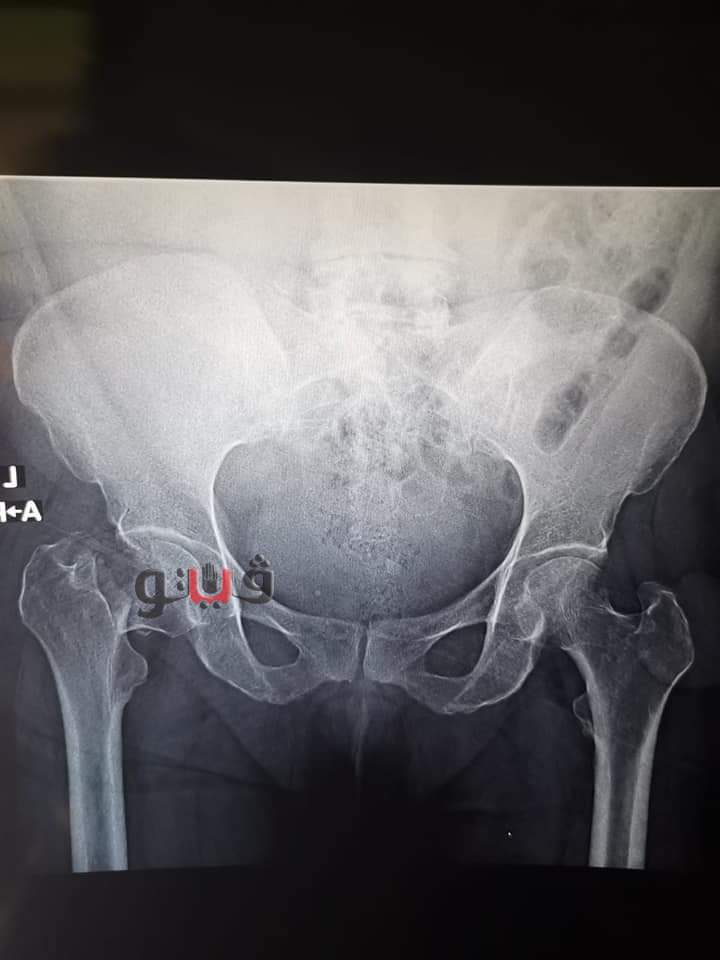

وأعلنت مديرية الصحة بجنوب سيناء انه حضرت المصابة لقسم اﻹستقبال الطوارئ بالمستشفى تعاني من أﻵم شديدة أعلى الفخذ الأيسر وبتوقيع الكشف والفحص السريري للمريضة وإجراء الفحوصات الطبية اللازمة من إختبارات الدم واﻷشعات واستخدام أشعة السي آرم تأكد وجود كسر بعنق عظمة الفخذ الأيسر .